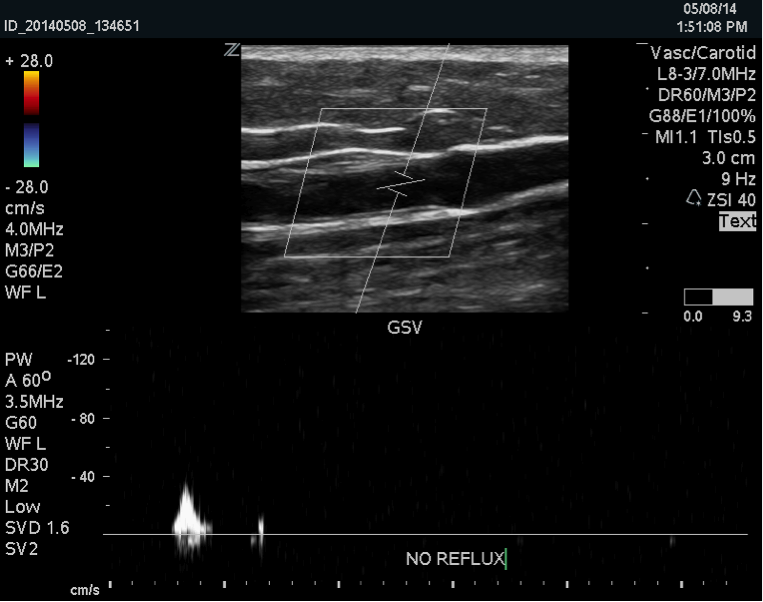

A deep vein thrombosis (DVT) is a blood clot in one of the veins in the deep venous system. There are 2 types of veins in the legs, deep and superficial. Deep veins are deep within the muscle and are responsible for 90% […]